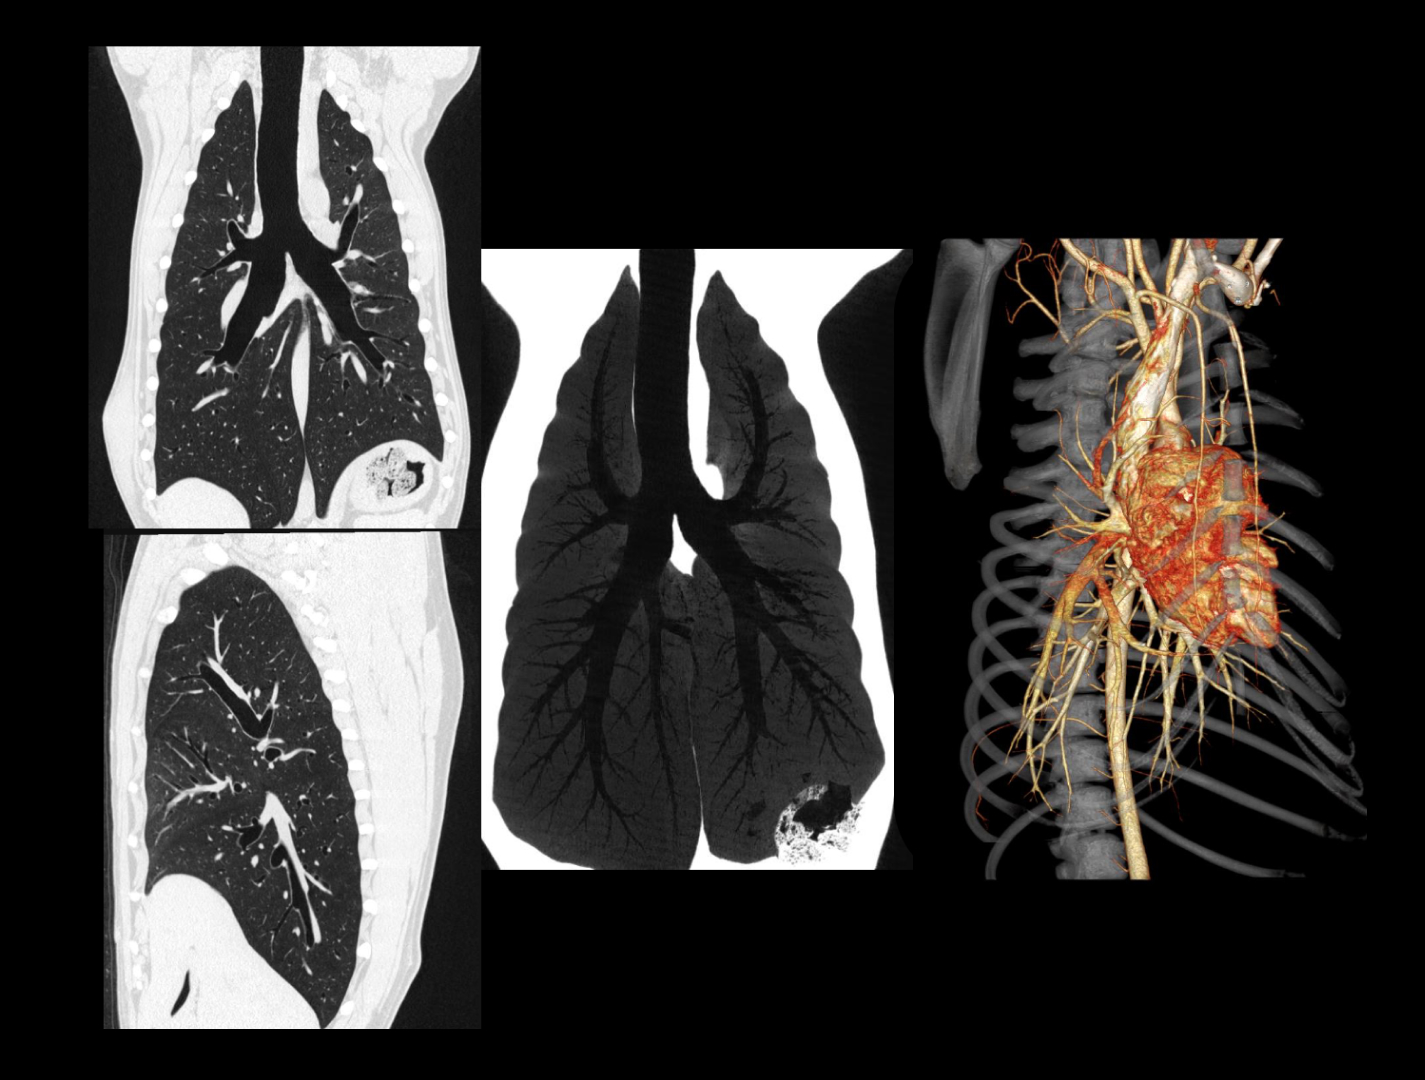

онкология и хирургия

SinoVision AlphaCT 358 Plus — компьютерный томограф на 64 среза. Устройство позволяет получать изображения высокой чёткости с помощью современной интеллектуальной платформы.

Универсальный томограф AlphaCT 358 Plus позволяет получать изображения высокой чёткости.

Виртуальная эндоскопия, позволяющая воссоздать внутреннюю структуру полых органов животных, что может быть актуально, например, при планировании предстоящей операции.

• Интеллектуальная система обработки изображения

• Патентованный детектор V-PIXEL